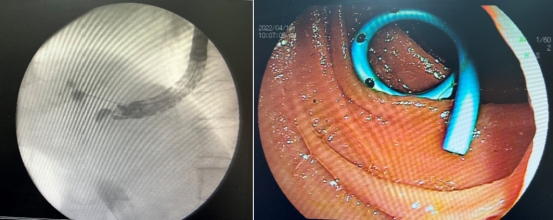

经过科内会诊,决定采用目前最先进的经超声内镜引导下进行胆汁引流(EUS- BD),祝喜萍凭借丰富的经验,在超声内镜引导下,顺利将导丝经胃壁穿入肝内胆管,再由胆总管经十二指肠乳头部进入十二指肠腔的“完美顺行”插管方式,成功放置胆道内支架,梗阻的胆汁顺利流出。术后,患者腹痛发热症状消失,2日后康复出院。

左图:超声内镜成功穿刺胆管并顺行留置导丝

右图:成功留置胆道支架